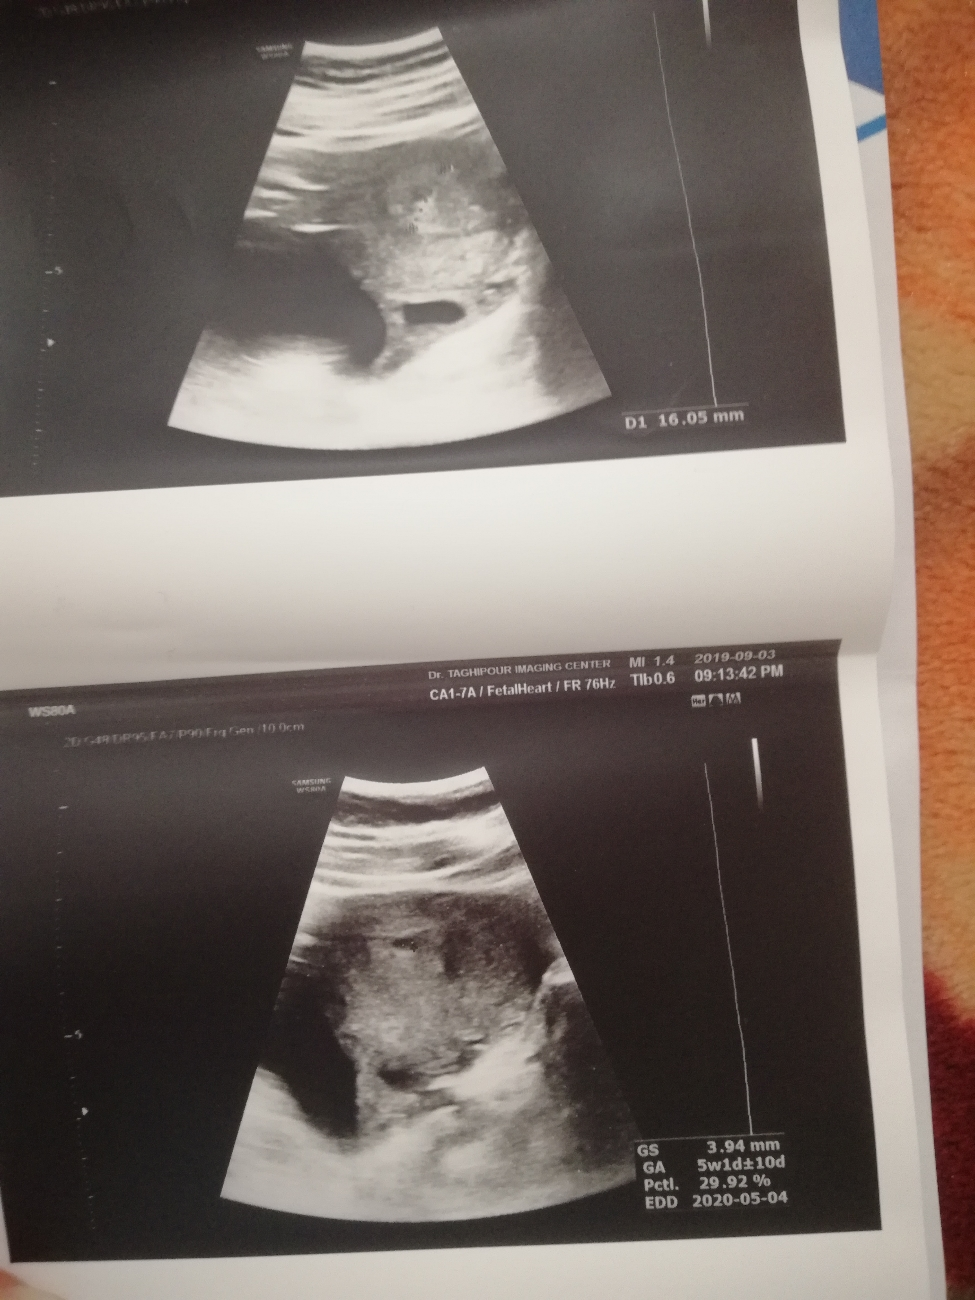

سلام دکترعزیز.من دوهفته قبل سونو انجام دادم که فقط ساک تشکیل شده بود بدون کیسه زرده وجنین که عکس رو براتون میذارم.و گفتن پنج هفته و یک روزم هست چون چیز سنگین بلندکردم افتادم به لکه بینی وخونریزی وسقط شد بدون هیچ بقایایی.

سقط پنج هفته و یک روز

من چون افتادم به لک رفتم سونو که دو روز بعدهم سقط شد. سن بارداری پنج هفته وفقط ساک بود.سوال من اینه جنینی نبوده لازمه مثل سقطهای هفته بالا سه تا شش ماه صبرکنم اخه میدونم همش بیست روز باردار بودم